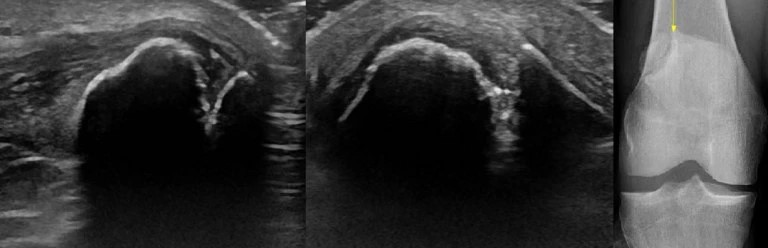

Фото